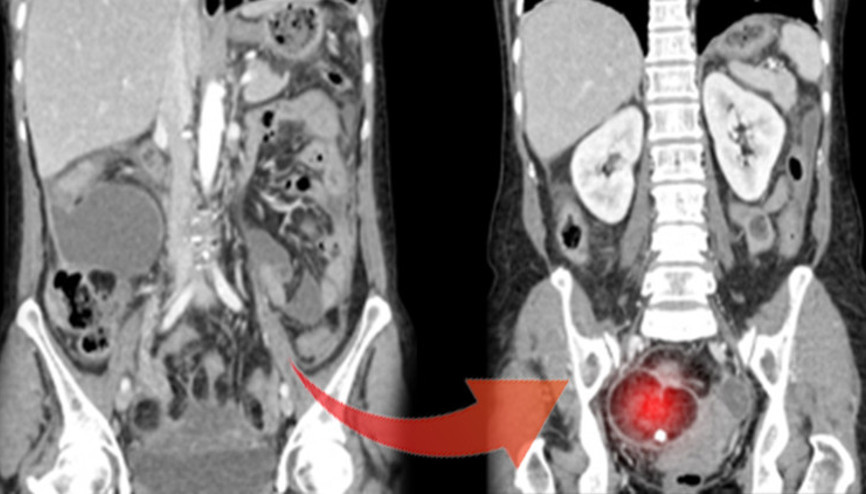

İstanbul’da yaşayan 24 yaşındaki genç kadın, karın şişliği ve gaz sancısı şikâyetleriyle doktora başvurdu. İlk başvurduğu merkezde sorunun sindirim sisteminden kaynaklı olduğu düşünülerek kendisine diyet programı önerildi. Ancak şikâyetleri aylar içinde artınca başka bir merkezde yapılan detaylı muayenede, karnında 45 santimetre büyüklüğünde ve 5 kilogram ağırlığında kist tespit edildi.

#Çikolata KistiÜreme çağında olan bir kadında kist için yapılan ameliyatlarda temel hedef yumurtalıkların korunması ve yalnızca kistin çıkarılmasıdır. Ancak kistin kansere bağlı olduğu düşünülüyorsa ve ameliyat esnasında yapılan hızlı patolojik inceleme kanser tanısını doğruluyorsa, bazı çok özel durumlar hariç, yumurtalığın alınması tedavi için yeterli değildir. Bu durumlarda standart yumurtalık kanseri ameliyatını uygulamak tedavi açısından çok önemlidir.